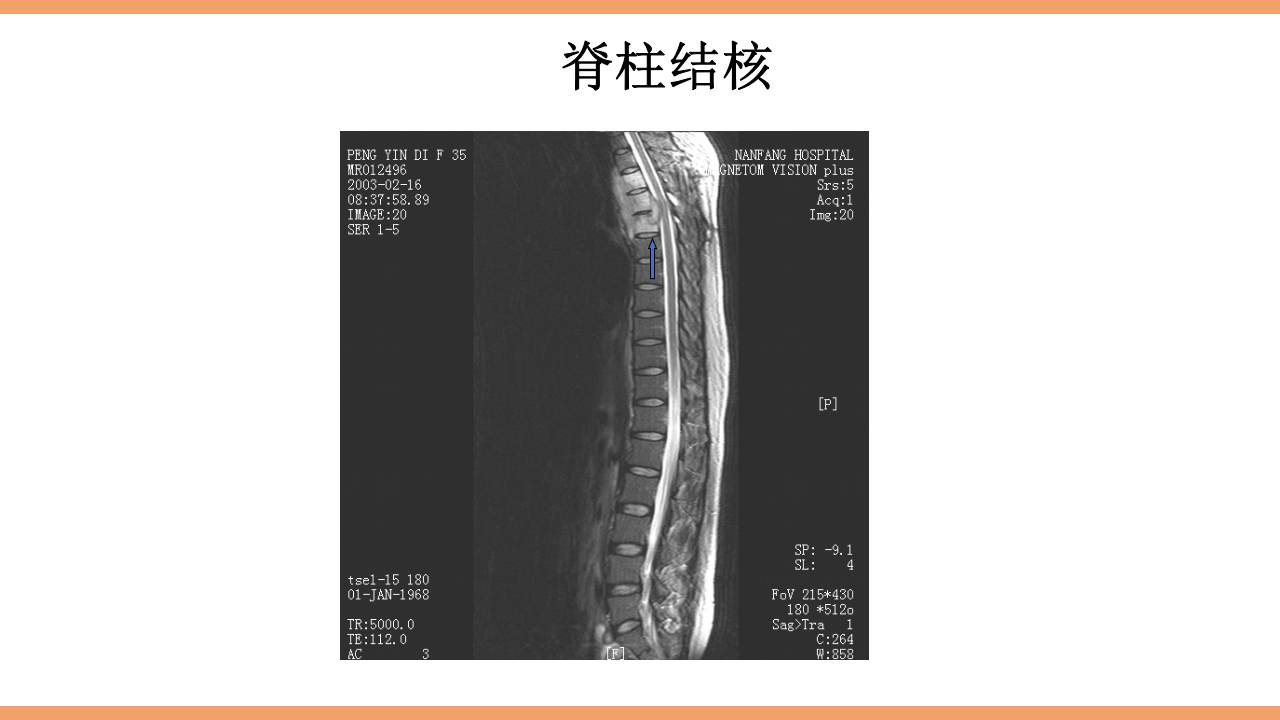

CONTENTS 目 录 1 结核简介 2 脊柱结核概论 3 病灶形成和发展 4 解剖位置 5 病理病因 6 分型 7 临床表现及症状体征 8 影像学及实验室检查 9 治疗 10 护理 11 治愈标准 12 出院指导 西医谓之为: 骨、关节结核:结核病菌侵入骨或关节内并在其中繁殖,出现 一系列的病理改变。 中医谓之为: 骨痨:由于结核杆菌侵入骨或关节而引起的化脓性病变,其病 发于骨,消耗气血津液,导致形体虚赢,缠绵难愈故其名为骨痨。 成脓破溃后,脓液中伴败絮状痰样物,可流窜他处形成寒性脓肿, 又名流痰。骨痨发于脊柱称之为脊柱痨、龟背痰。 胸椎结核为龟背痰,腰椎结核为肾俞虚 痰,骶尾椎结核为尾闾发。 1.脊柱结核是一种继发性病 变,约90%继发于肺结核.少 数继发于消化道结核、胸膜 结核或...